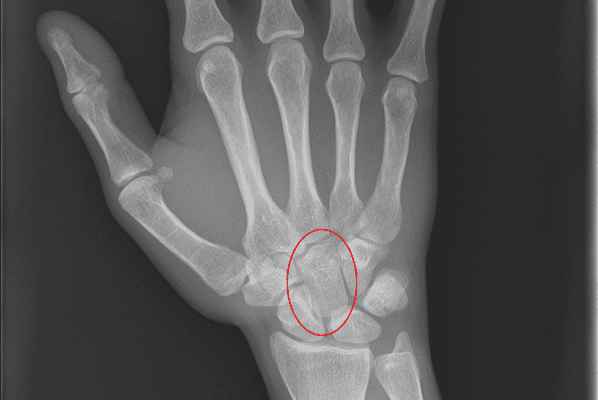

Carpal bone Fractures can be difficult to detect on conventional Xray and may require CT for diagnosis.

Where Carpal Fracture is suspected, X-rays in the anteroposterior (AP), lateral and oblique views are needed. Bone scans and CT scans are sometimes helpful if the fracture is not obvious on plain X-ray and should be considered where fracture is still suspected.

These are rare but devastating injuries. They can be associated with a carpal fracture. Fracture dislocations are twice as common as pure ligamentous dislocations. Isolated carpal dislocations are rare.

The most common Carpal dislocations are the lunate, the lunate with a scaphoid fracture, and perilunate dislocation.Carpal dislocations can lead to chronic pain and wrist instability. They are difficult to diagnose and are often missed.